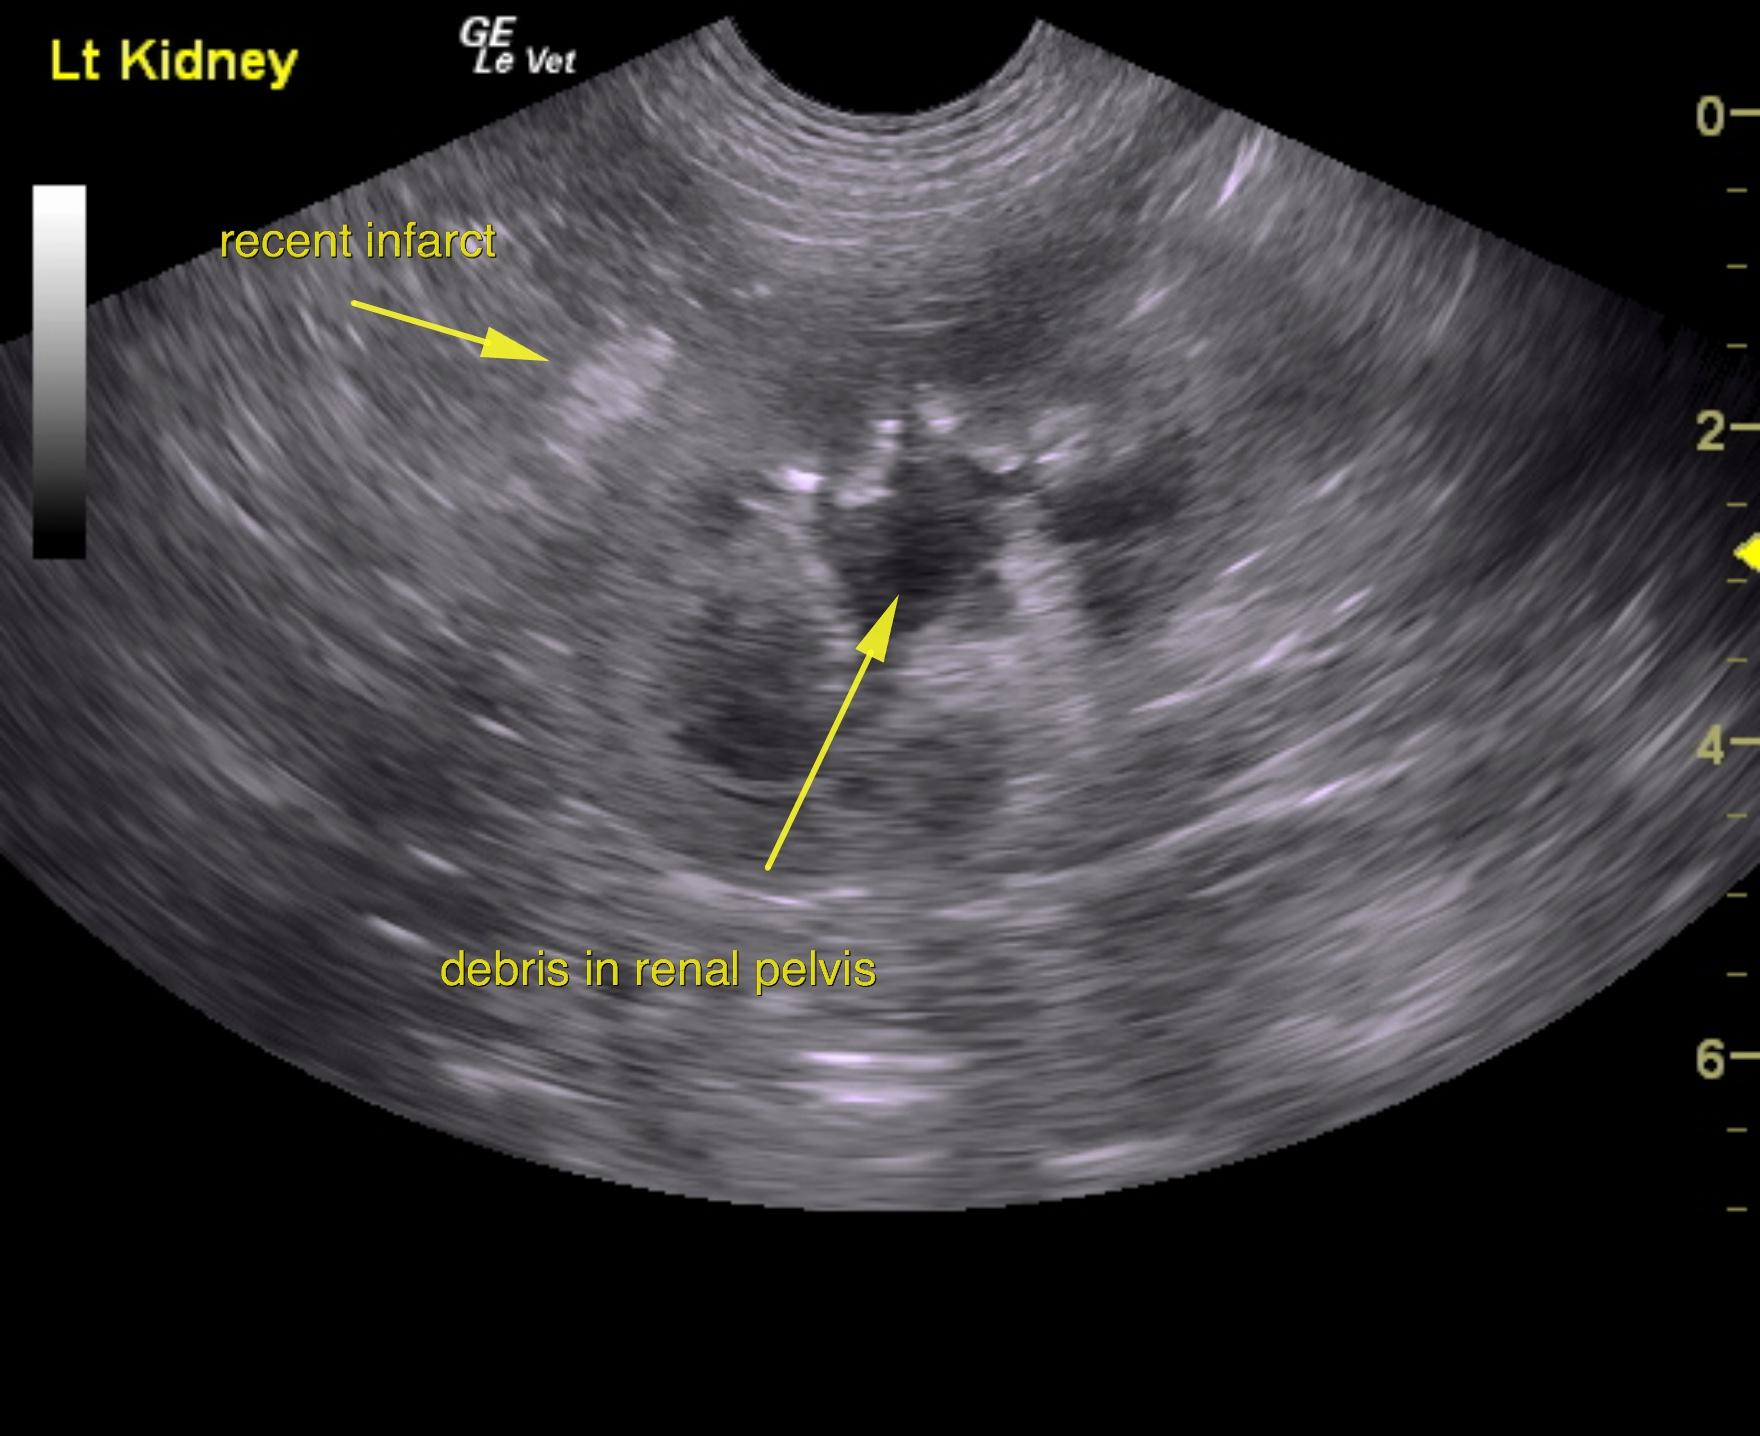

A 5-years-old male neutered Shih Tzu was presented for evaluation of urethral obstruction that had been managed with catheterization. Urinalysis showed SG of 1.008 and proteinuria. Abnormalities on CBC and serum biochemistry were neutrophilia and monocytosis, elevated phosphorus, and azotemia; the latter had improved after being catheterized.